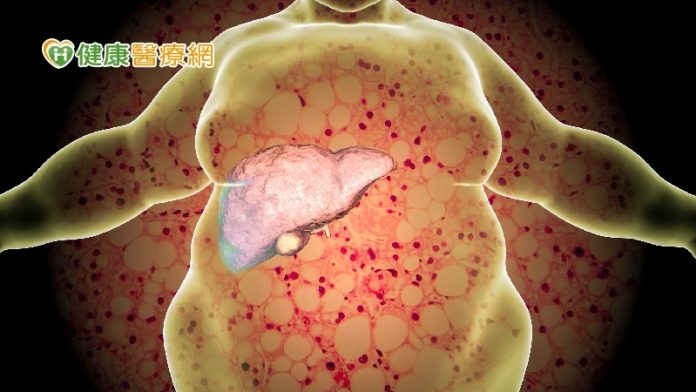

【健康醫療網/記者鄭宜芬報導】炸物配甜點讓人愛不釋手,但當心合併糖尿病會導致肝指數飆高。一位四旬男子有脂肪肝、糖尿病合併肝功能異常,肝指數最高飆到2百多,照超音波檢查看起來泛油光,「肝臟八成都被脂肪堆積!」即使服用護肝藥也無明顯成效。男子最後下定決心減重,每天夜跑瘦下20公斤,終於不用再吃血糖藥,重度脂肪肝也回歸正常。

國外研究指出,身體質量指數(BMI)數值越高,罹患脂肪肝的機率也越高。林新醫院胃腸肝膽科主任張瑞旻說明,脂肪肝常見的成因包括酗酒、糖尿病、血脂過高、基因遺傳、體重過重或代謝異常、減重過快、飲食不正常及服用類固醇等藥物所引起,會造成脂肪代謝異常,堆積成脂肪肝。

脂肪肝與糖尿病互為因果關係,94%脂肪肝患者有高血糖風險,脂肪代謝異常會造成胰島抗性增加,胰島被迫加班久了就會變成糖尿病,糖尿病又會造成身體代謝異常加重脂肪肝,形成惡性循環。

根據107年癌症登記資料顯示,24.3%肝癌與脂肪性肝炎有關。醫師提醒,BMI大於25(過重)之民眾,若合併肝功能異常、慢性肝炎,就屬於肝硬化之高風險族群,一旦等到皮膚泛黃出現黃疸、易疲勞倦怠時,恐為時已晚,容易罹患嚴重肝病。建議有脂肪肝之民眾,每半年應做肝功能超音波檢查,檢查肝臟表面是否有粗糙或硬化。